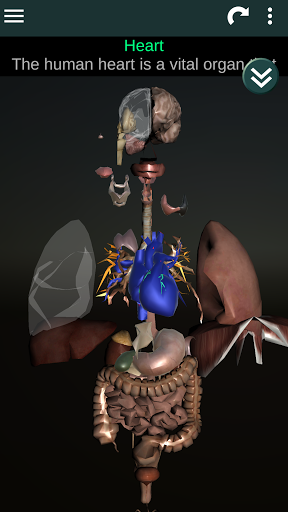

Toont een 3D-anatomisch model van de belangrijkste organen van het menselijk lichaam en een beschrijving van elk orgaan.

* Spijsverteringsstelsel, inclusief de maag, dunne darm, dikke darm, en een animatie van dit systeem.

* Ademhalingssysteem, inclusief de luchtpijp, bronchiën, longen en een animatie van dit systeem.

* Hart, dat de atria, ventrikels, aorta en een animatie van dit orgel omvat.

* Gemakkelijk te openen en te navigeren (zoom, 3D-rotatie).

* Beschrijvingen van elk orgel.